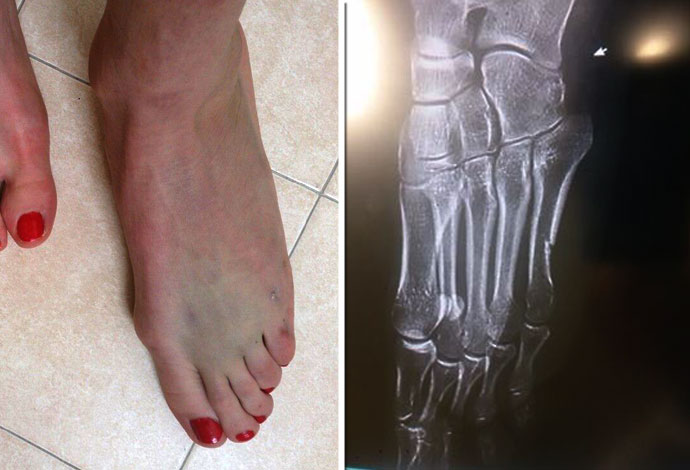

Justyna Kowalczyk Feet

Justyna Kowalczyk Feet Pics